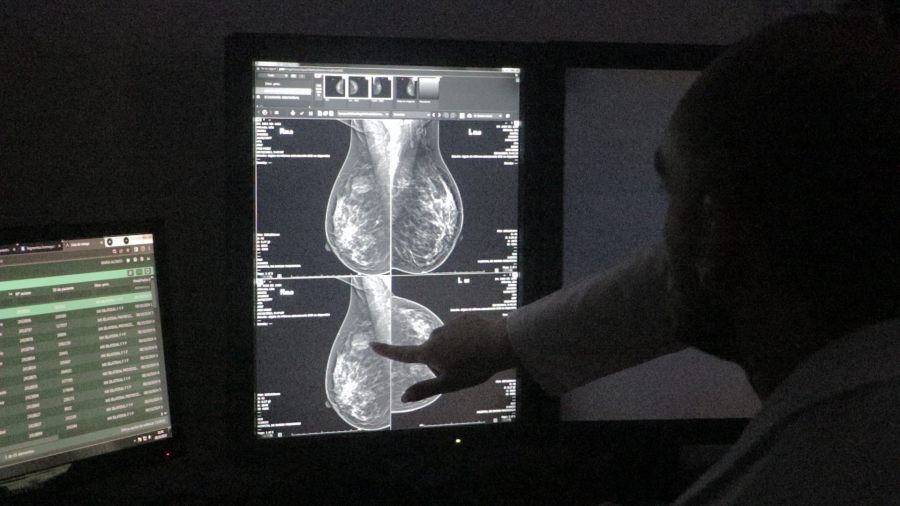

Durante todo el mes, el Servicio de Diagnóstico por Imágenes del Hospital Dr. Ramón Madariaga ofrece mamografías sin turno previo ni pedido médico, de lunes a viernes, de 14,00 a 00,00 horas.

El Dr. Carmona destacó la relevancia de la prevención como principal herramienta para reducir la mortalidad por cáncer de mama y de cuello uterino. “En este mes Rosa, queremos convocar a todas las pacientes que se encuentren en edad de control a partir de los 40 años a realizarse estudios imagenológicos, como la mamografía, ecografía mamaria y resonancia, que son fundamentales para el diagnóstico temprano”, señaló.

Asimismo, subrayó que el examen clínico y el autoexamen continúan siendo las primeras herramientas para la detección de anomalías, pero que deben complementarse con estudios por imágenes. “La mamografía y la ecografía son los elementos principales en el diagnóstico temprano de la patología mamaria, especialmente en la oncológica”, agregó el profesional.

El Hospital dispone de un sistema que permite realizar un número determinado de mamografías diarias, priorizando el acceso a mujeres en edad de riesgo. Carmona recordó que es recomendable realizar una mamografía y una ecografía mamaria por año a partir de los 40 años, tanto para mujeres con como sin antecedentes familiares de cáncer de mama.

El cáncer de mama se origina cuando las células del tejido mamario comienzan a crecer de manera anormal y descontrolada. Es el tipo de cáncer más frecuente en mujeres a nivel mundial, pero detectado a tiempo tiene altas probabilidades de tratamiento exitoso. La mamografía es el método más eficaz para su detección temprana.